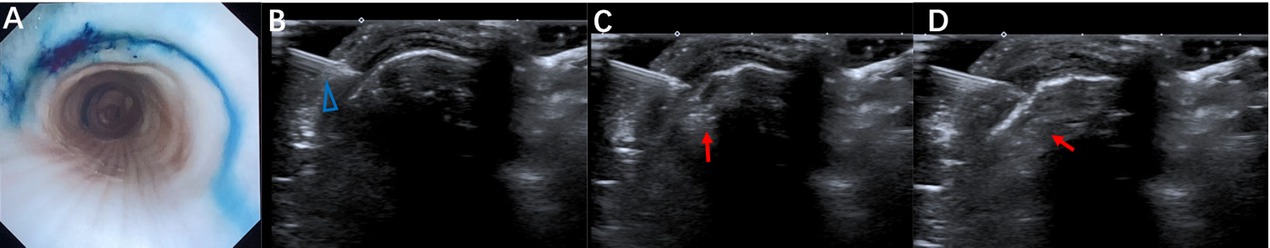

Real-time bronchoscopic monitoring was conducted for the process of submucosal methylene blue injection (Figure 2A) to the ex vivo porcine trachea as guided by POCUS (Figure 2B–2D). The location and distribution of the submucosal injection guided by POCUS was clearly shown with the shape of a semicircle between the adjacent tracheal rings. It also demonstrated the whole process of the submucosal injection and the dynamic thickening of the submucosal layer following the submucosal injection. The location of the injection point of the needle presented with more intense staining of methylene blue compared to the peripheral area, with immersion of the dye.

Correspondence of the bronchoscopic view of the inner tracheal wall with the submucosal injection of methylene blue guided by transcutaneous POCUS (A) Bronchoscopic manifestation of ex vivo porcine trachea after submucosal injection of methylene blue guided by transcutaneous POCUS. (B–D) The process of submucosal injection of methylene blue guided by POCUS. The blue triangle indicates the injection needle. The red arrow indicates the thickening of the submucosal layer with the medication injection. POCUS: point-of-care ultrasound.